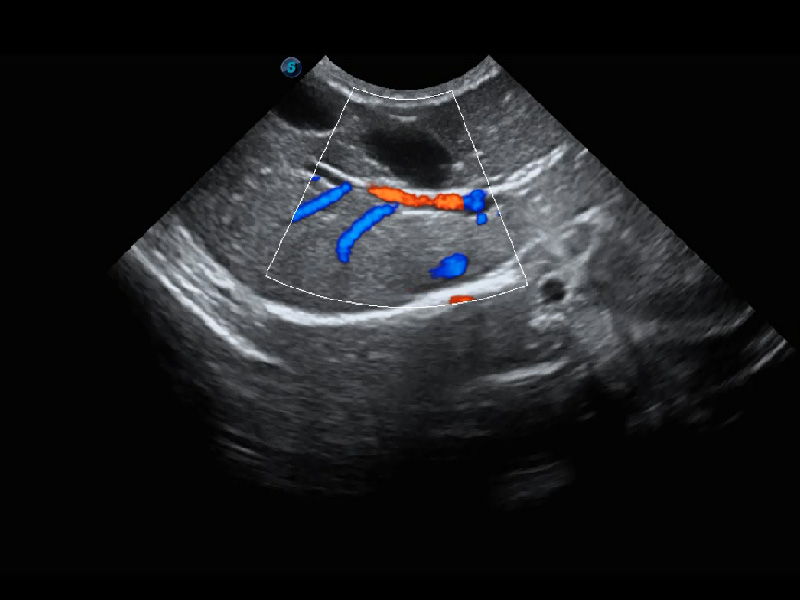

ProPet 60 作為一款高端臺(tái)式動(dòng)物超聲設(shè)備,為動(dòng)物醫(yī)生的日常診斷提供了一系列貼合動(dòng)物臨床需求、解決臨床實(shí)際問(wèn)題的高級(jí)成像功能。憑借全系列高清探頭,滿(mǎn)足醫(yī)生對(duì)腹部、心臟、生殖、淺表、肌骨等成像的所有需求,切實(shí)幫助您提升檢查效率,提高診斷信心。